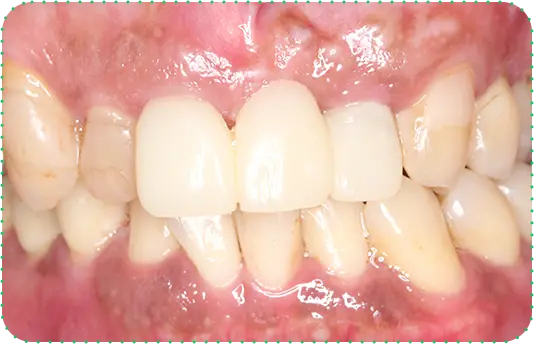

主訴

上の前歯が抜けそう

治療期間

6か月

治療費

30万円

治療内容

右上1番を抜歯後に骨と歯茎を増やし、隣の歯の裏側を少量削り、接着性ブリッジにて修復

治療のリスク

咬み合わせによっては、セラミックが欠ける可能性があります。